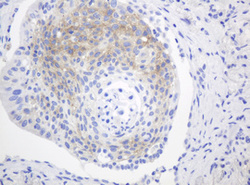

Supportive validation

- Submitted by

- OriGene (provider)

- Main image

- Experimental details

- Immunohistochemical staining of paraffin-embedded Carcinoma of Human lung tissue using anti-FGFR3 mouse monoclonal antibody. (Heat-induced epitope retrieval by 10mM citric buffer, pH6.0, 120C for 3min, TA801078)

- Validation comment

- IHC